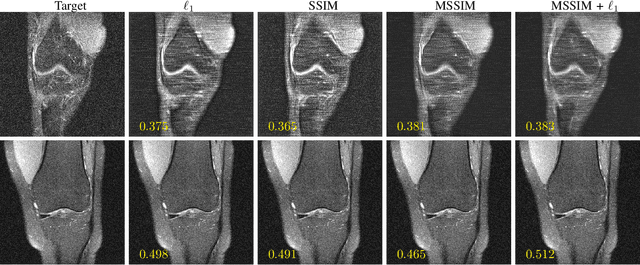

Abstract:Adaptive intelligence aims at empowering machine learning techniques with the additional use of domain knowledge. In this work, we present the application of adaptive intelligence to accelerate MR acquisition. Starting from undersampled k-space data, an iterative learning-based reconstruction scheme inspired by compressed sensing theory is used to reconstruct the images. We adopt deep neural networks to refine and correct prior reconstruction assumptions given the training data. The network was trained and tested on a knee MRI dataset from the 2019 fastMRI challenge organized by Facebook AI Research and NYU Langone Health. All submissions to the challenge were initially ranked based on similarity with a known groundtruth, after which the top 4 submissions were evaluated radiologically. Our method was evaluated by the fastMRI organizers on an independent challenge dataset. It ranked #1, shared #1, and #3 on respectively the 8x accelerated multi-coil, the 4x multi-coil, and the 4x single-coil track. This demonstrates the superior performance and wide applicability of the method.